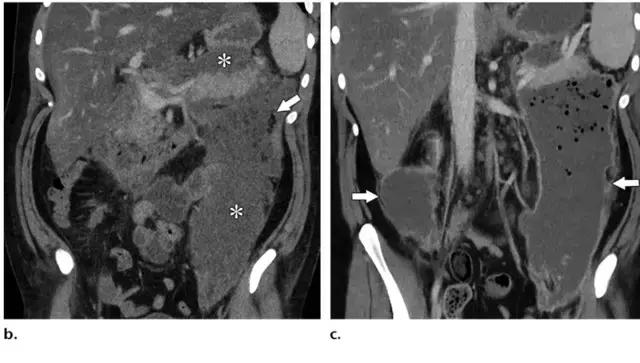

ANCs 也含有大量液体,和 APFCs 的鉴别是 ANCs 含有非液性成分,比如实性成分或脂滴。如果有碘对比剂禁忌证,平扫 CT 如果能发现脂性密度对确定坏死及诊断 ANCs 具有重要帮助(图 9)。

在胰腺炎早期,APFC 和 ANC 的鉴别比较困难。发病后 2 周的影像学检查对鉴别两者具有重要意义。所有与坏死胰腺实质相通的胰周异常病灶即使看不到非液性碎片也应诊断为 ANC。

图 9 41 岁急性胰腺炎女性患者合并 ANC。发病 9 天后的 CT 平扫图像示胰腺和胰周密度对比度下降,因此难以确定胰腺实质坏死部位。但小脂滴(箭头)的出现和整体不均质密度均提示该患者为坏死性胰腺炎伴 ANC